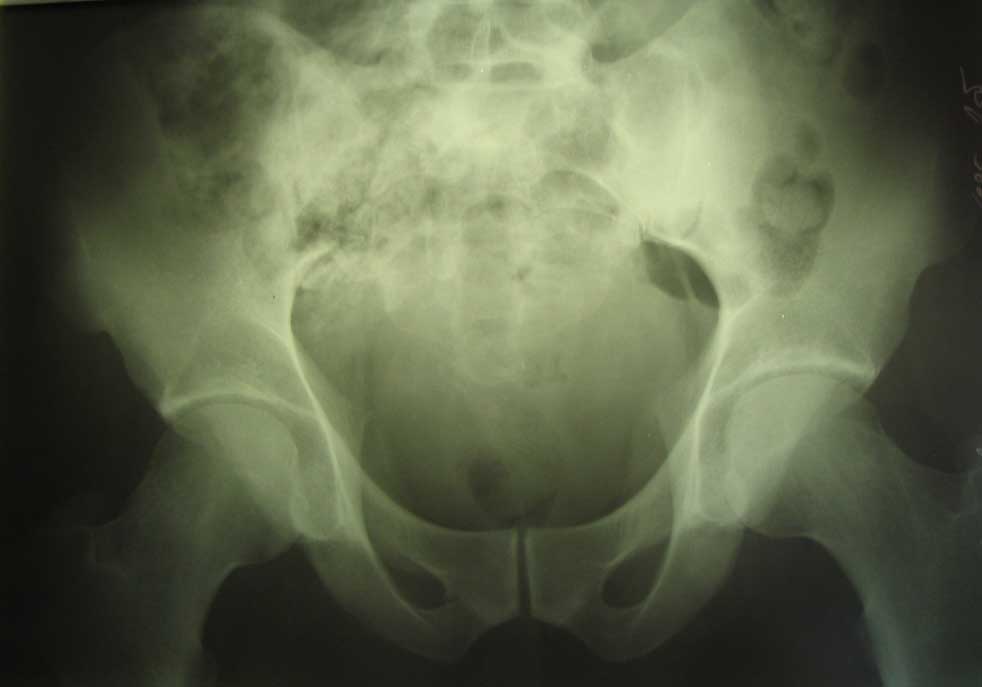

живот |  крестец |  плечо |  спина |  снимок |  снимок-схема | Поработал, блин... Шмальнули в него из"калаша" почти в упор: сквозное ранение живота с повреждением подвздошной кишки (вход -правая подвздошная область, выход на крестце), касательное левого плеча (пуля прошла подкожей) и практически царапина на правом плече.Ранение - 6.03, в этот же день прооперирован - ушивание ран подвздошной кишки и т.н."обработка" раны левого плеча (зачем-то удалили отслоенный мостик кожи... :-/ ). Черездень - релапаротомия, резекция участка подвздошной кишки. До России он добрался только25.03 (КАК он добрался - отдельная история...), с хорошо гноящимися и разошедшимися ранамина передней брюшной стенке, крестце и левом плече (см. фото в аттаче). В принципе с ранамивсе понятно, санация-заживление-пластика... И это не самое страшное... Сегодня выполнена рентгенография - оскольчатый перелом крестцово-подвздошного сочленениясправа. Плюс к этому - выраженный парез правой н/конечности с выпадением чувствительностии парестезиями (хотя частично чувствительность сохранена, и какое-то подобие произвольныхдвижений тоже есть). Поэтому хотелось бы спросить - какова должна быть тактика в отношенииперелома (режим, лекарства и т.п.) и в отношении неврологии? Также интересуют возможныеисходы... Приветствуются все мысли, замечания и предложения... -- С уважением, Андрей Башлачев mailto:bashlachev@yandex.ru Ивановская государственная медицинская академия, кафедра хир. болезней пед. ф-та

Учитывая, что основная часть сустава цела, хирургическая стабилизация не требуется. Там, видимо, перестрелены корешки. Медикаменты тут никакие не помогут, разве что если будут каузалгии, тогда добавить финлепсин или амитриптилин. А все-таки какие поточнее неврологические выпадения? Стопа висит? Надо посоветоваться с нейрохирургами по поводу целесообразности ревизии.

Сегодня консультирован зав. отд. гнойной травматологии и зав. отд. спинальной нейрохирургии. Пришли к выводу, что в первую очередь необходимо заниматься крестцом (профилактировать остеомиелит, дообследовать, возможно - фиксировать тазовое кольцо), для чего больного нужно переводить в травму. Что касается неврологических проявлений - это все вторично (из-за контузии - отека - и т.п.).

в отношении перелома. Интересно посмотреть проекции "inlet","out let" возможно они помогут определиться в отношении тактики лечения повреждения таза.